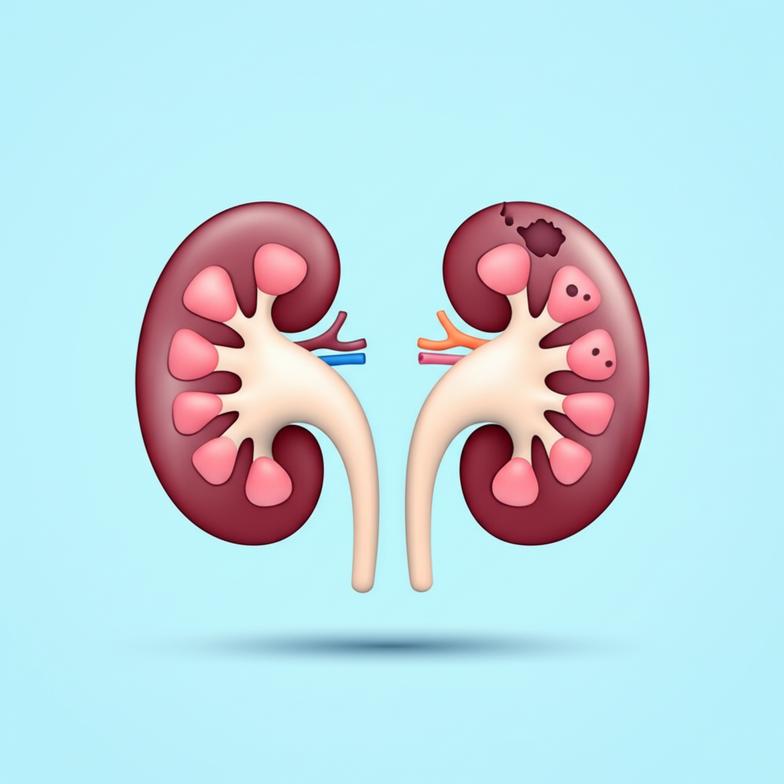

ทำความเข้าใจ “ไตเสื่อม” สาเหตุและสัญญาณเตือนที่คุณต้องรู้

ไตเสื่อม หรือโรคไตเรื้อรัง (CKD) คือภาวะที่ไตไม่สามารถกรองของเสียออกจากเลือดได้อย่างเต็มประสิทธิภาพ ซึ่งสำคัญต่อสมดุลร่างกาย การเข้าใจสาเหตุและสัญญาณเตือนจึงเป็นกุญแจสำคัญในการตรวจพบและรักษาแต่เนิ่นๆ เพื่อป้องกันโรคสู่ระยะรุนแรง

สาเหตุหลักของโรคไตเสื่อม:

- โรคเบาหวาน: สาเหตุอันดับหนึ่ง น้ำตาลในเลือดสูงทำลายหลอดเลือดเล็กๆ ในไต

- โรคความดันโลหิตสูง: ควบคุมไม่ได้ เพิ่มแรงดันในหลอดเลือดไต ทำให้ไตทำงานหนักและเสื่อม

- โรคไตอักเสบ: การอักเสบของหน่วยไต อาจเกิดจากภูมิคุ้มกันผิดปกติหรือติดเชื้อ

- นิ่วหรือทางเดินปัสสาวะอุดตัน: การอุดตันสะสมปัสสาวะ เพิ่มแรงดันในไต ทำให้เกิดความเสียหาย

- การใช้ยาบางชนิดนานๆ: ยาแก้ปวดกลุ่ม NSAIDs หรือยาปฏิชีวนะบางชนิด หากใช้โดยไม่ระวังอาจส่งผลต่อไต